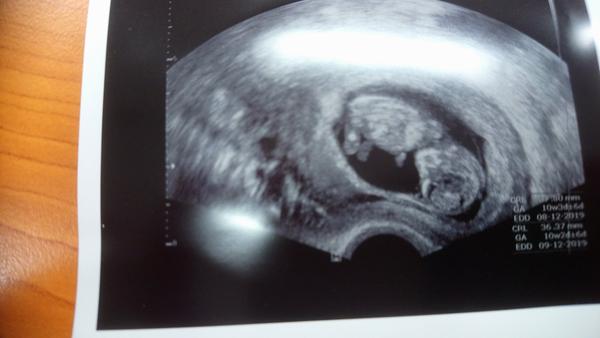

Tak jsem se vratila z kontroly, vsechno v poradku, mimi ma 2,5 cm, myslim ze 9+0 tt. Bylo krasne videt, vrtelo se... Laska na prvni pohled 🙂 A dokonce mi je od vikendu o trosku lip, po naprosto hroznych 14-dnech... Takze ja mam dnes radostny den, a preju taky radostny vam vsem 🙂

Ahoj holky! Tak druhá kontrola je úspěšně za námi má dvě ruce dvě nohy tak snad to bude dobrý 😀 Bylo super se dívat na té obrazovce jak se tam furt vrtí, málem jsem se tam rozbrečela 😅 Momentálně jsem 10+4 a genetika mě čeká za tři týdny, všem ostatním co je čeká kontrola přeji ať je vše O.K